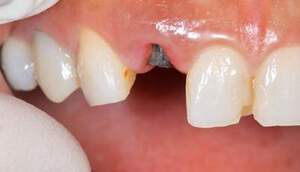

左の写真は歯が歯肉縁上にないのがわかります。右では歯肉縁上に1周にわたって歯牙があるのがわかります。

レントゲンで見ても、右上2では歯質が歯肉縁上にのこっていない。しかし歯根は長いのでMTMの適応症例です。

治療前で残存歯質がほとんどみられません。

残存歯質はないが、歯根は長いことを確認。